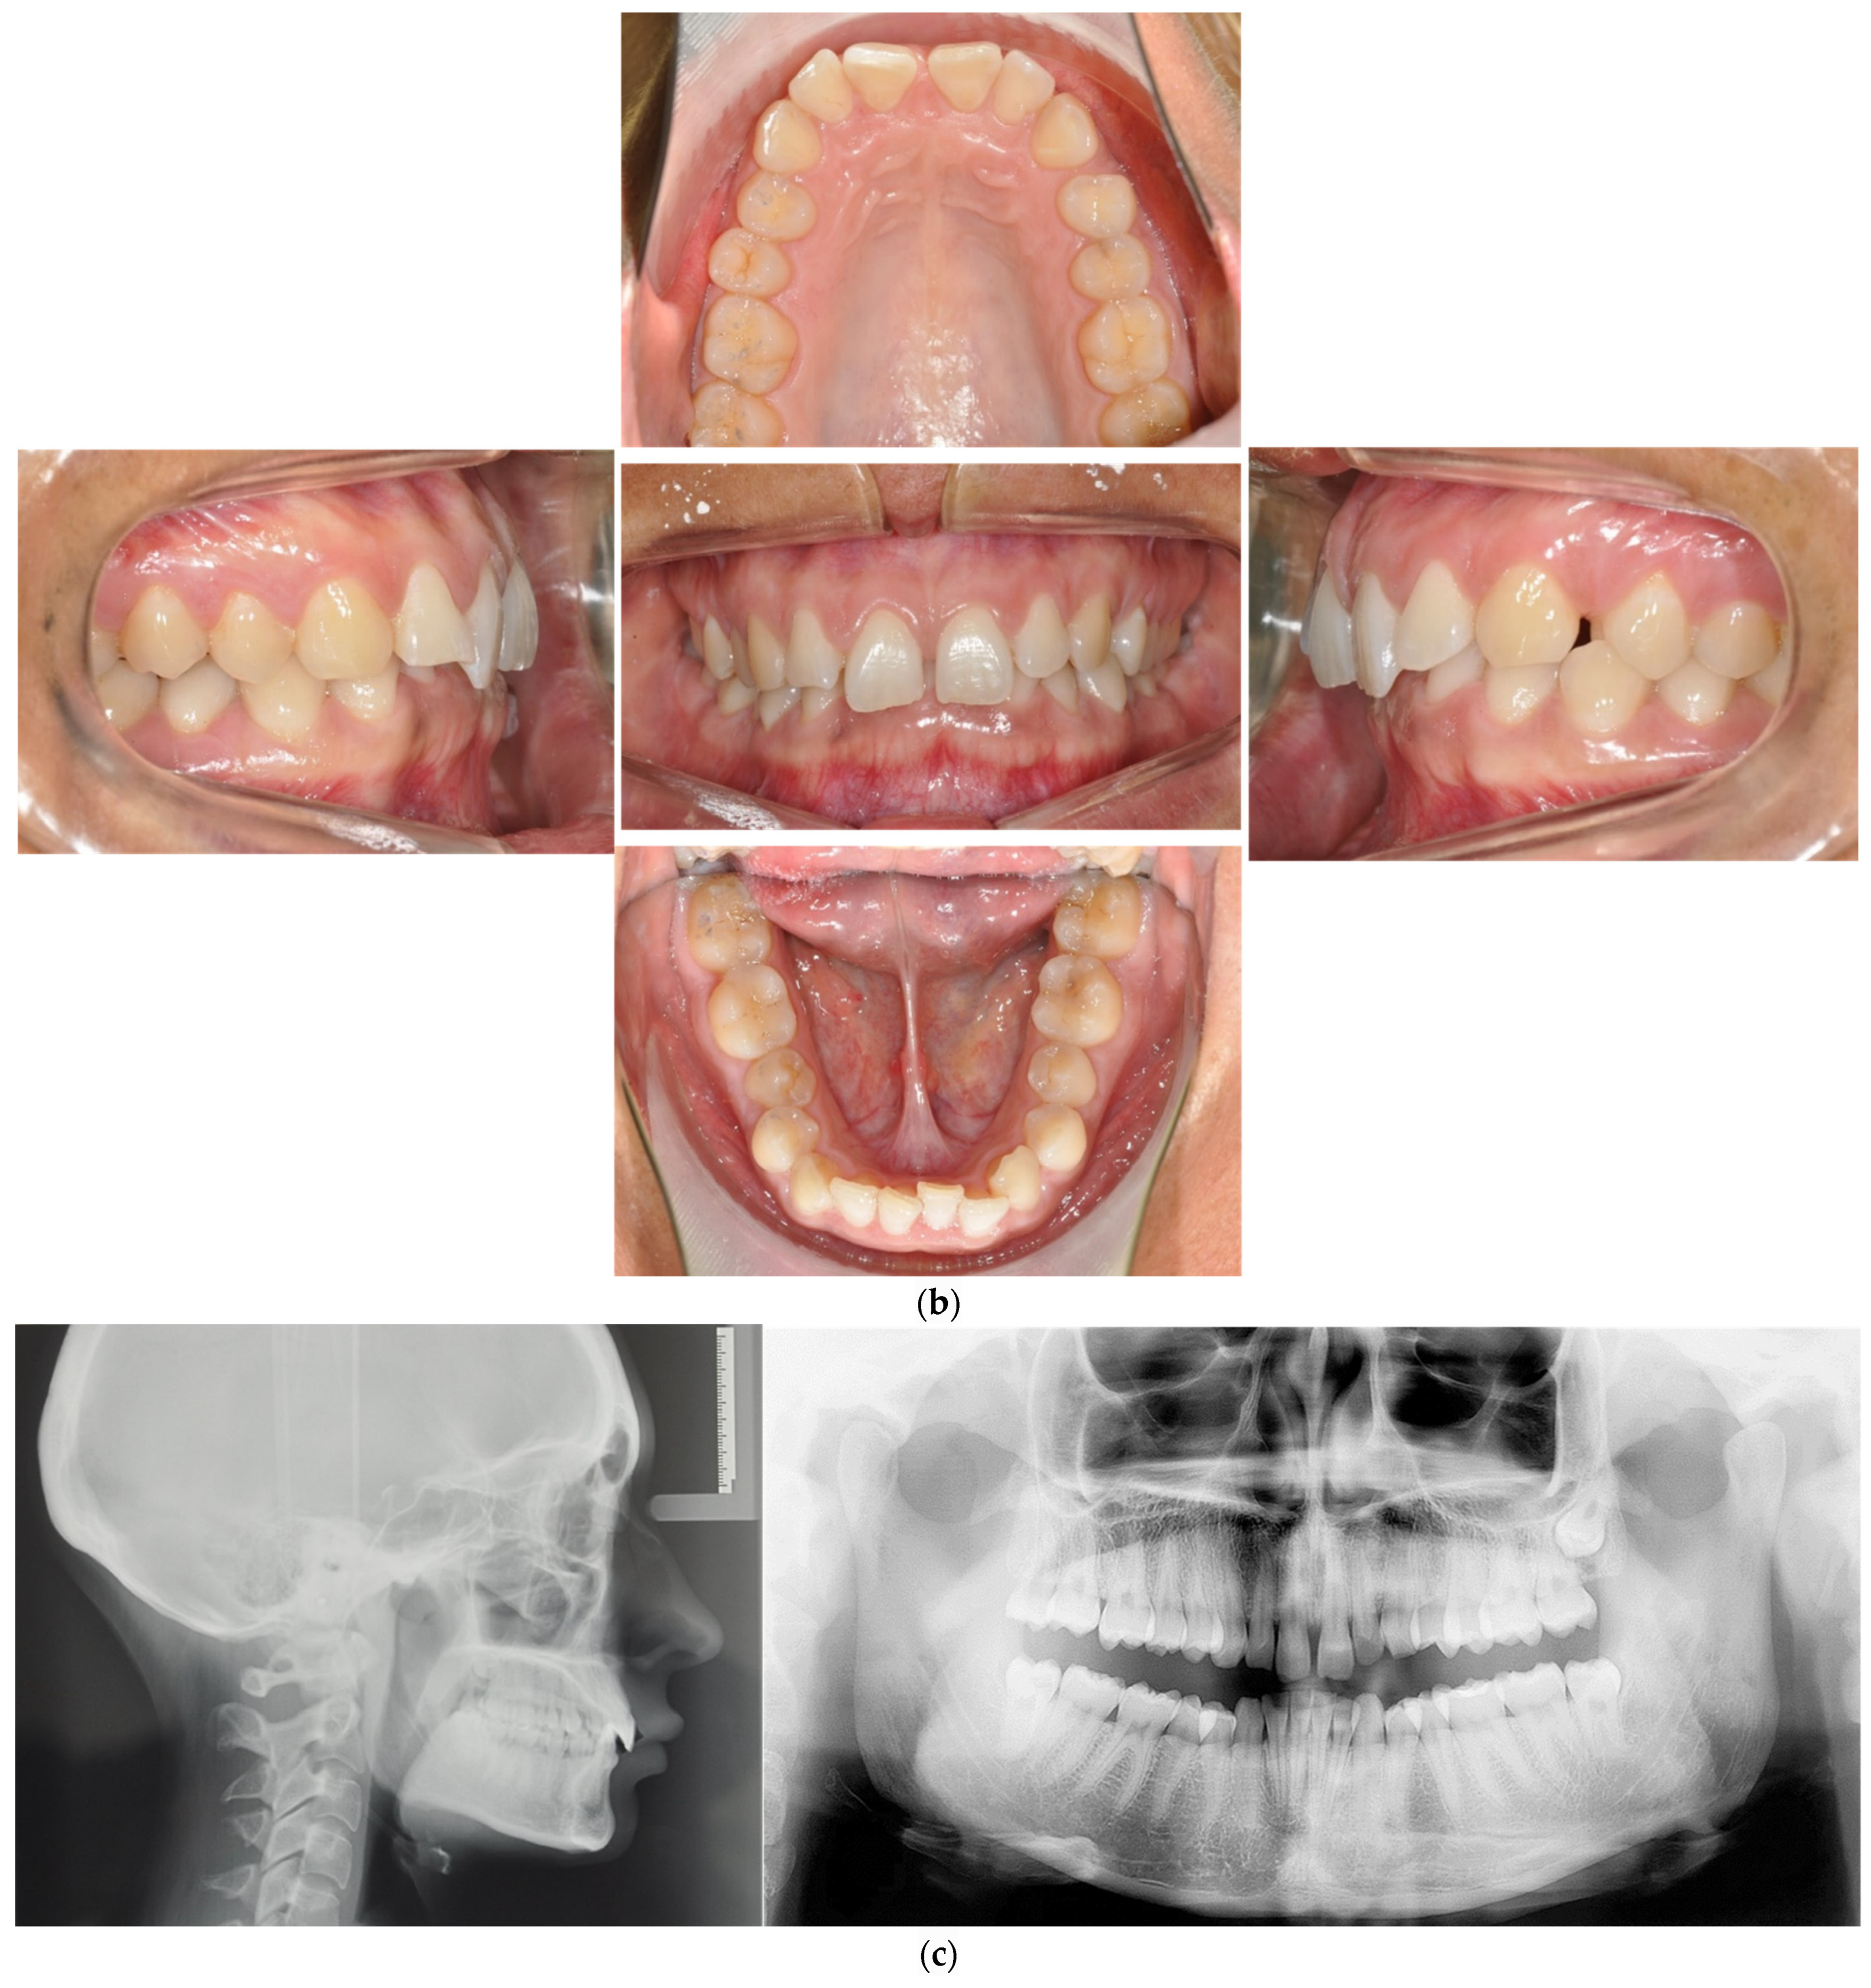

4.1. Case 1: Class II Division 2 with a Deep Bite